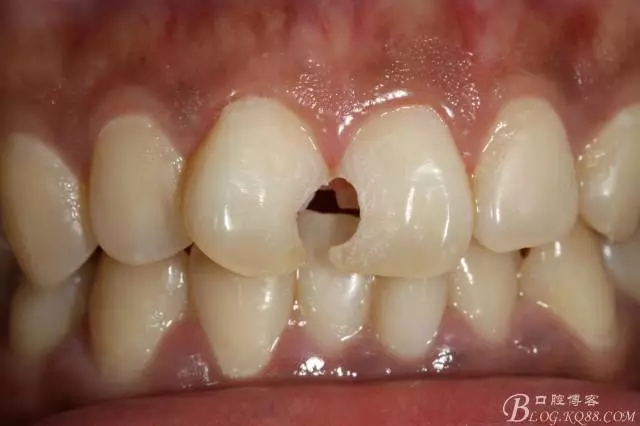

去腐備洞后

3mz250充填完成即刻照